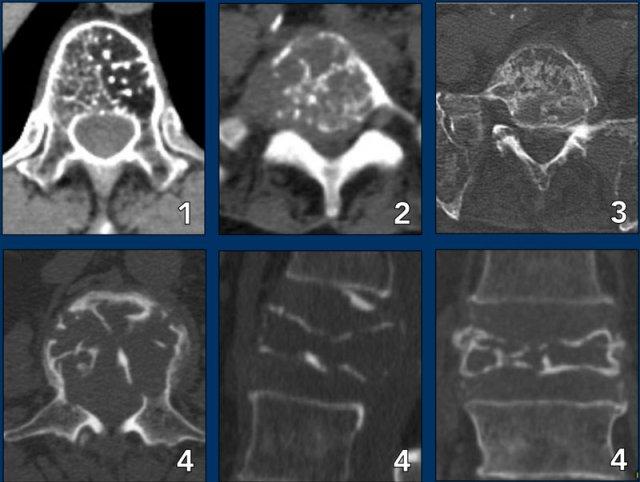

Spine lesions

Here some typical examples of bone tumors in the spine.

- Hemangioma.

- Metastasis.

- Multiple myeloma.

- U tương bào: đốt sống dẹt.

Hình ảnh ‘Não Thu Nhỏ’ của u tương bào ở cột sống có tính chất đặc trưng bệnh lý đủ để không cần sinh thiết (9).